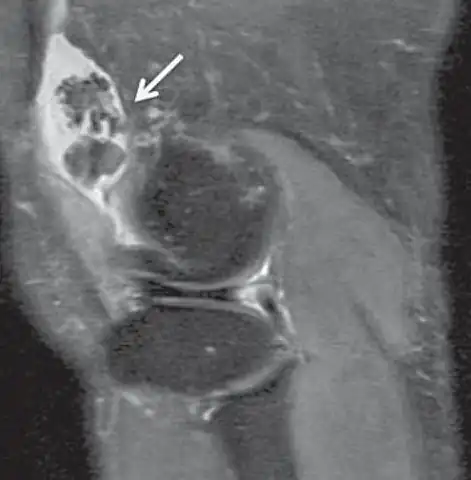

Proton density weighted | PD | Long TR (to reduce T1) and short TE (to minimize T2).[7] | Joint disease and injury.[8]

Proton density (PD)- weighted images are created by having a long repetition time (TR) and a short echo time (TE).[36] On images of the brain, this sequence has a more pronounced distinction between grey matter (bright) and white matter (darker grey), but with little contrast between brain and CSF.[36] It is very useful for the detection of arthropathy and injury.[37]